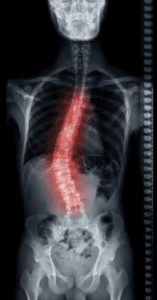

- A Twist of Fate: Traumatic scoliosis isn’t like that genetic curve some folks are born with. No, this one’s earned, and painfully so, through sudden trauma—a high-speed collision, a jarring impact. It’s a spinal deformity brought about by injury, not by nature.

- The Breaking Point: Accidents force unnatural angles on the body, and the spine takes the brunt. Vertebrae snap or shift, soft tissue tears. In traumatic scoliosis, it’s like your spine’s skeleton gets bent out of shape, and what was once straight is now painfully curved.

- Physical Manifestation: That ache in your back? It’s not just from sitting too long. For many with traumatic scoliosis, there’s visible misalignment—a hip that juts out to one side, a shoulder that doesn’t sit level. It’s the type of pain that gets into your bones and refuses to budge.

- Unnatural Curves: Stand in front of a mirror, and you’ll see it—a shoulder that droops or hips that tilt, like your body’s turned into a leaning tower.